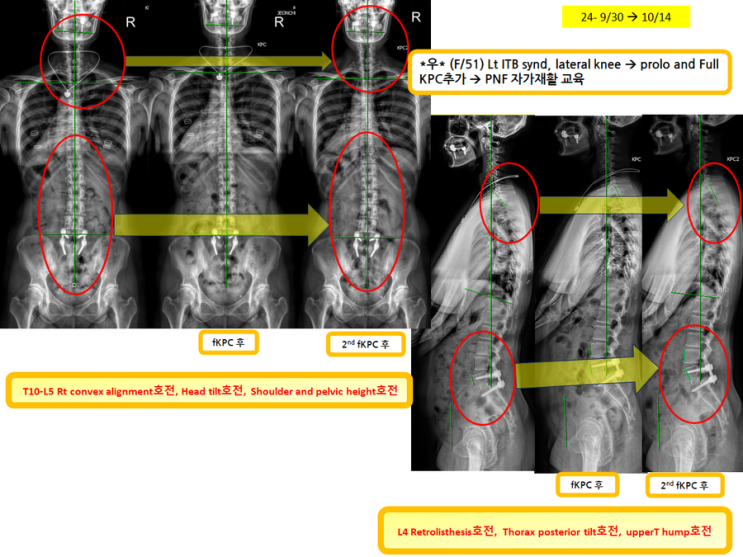

무릎외측통증이 주소인 환자분!(녹는실KPC치료는 엑스레이 호전을 10분만에 확인)

무릎외측통증이 주소인 환자분! (녹는실KPC치료는 엑스레이 호전을 10분만에 확인) 전에 했던 장경인대 ...